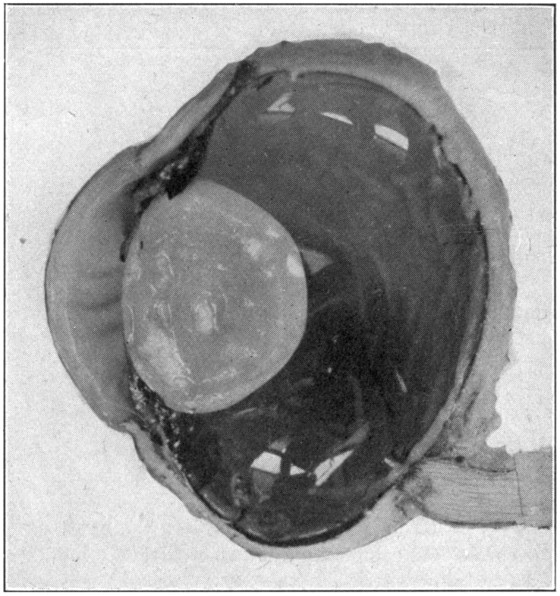

Fig. 7—Photograph of dissected hyaloid membrane (A), with pigmented indentations of the ciliary processes, the suspensory ligament (B), and the crystalline lens in its capsule (C). (Page 34.)

Many times a considerable amount of pigment from the second tunic will remain attached[34] to the processus zonuloe. This pigment may be easily removed by scraping it off with the sharp edge of the scalpel or by brushing it off with a soft, wet tooth-brush.

It is unwise to use alcohol as a preservative because it produces an almost immediate opaqueness and hardness which spoils the specimen for further study.

This description may give the impression that the dissection is a lengthy one; however, it can be done by an expert in two or three minutes; by a beginner in five or six minutes.

For purposes of demonstration or study the specimen should be placed in a small bottle or a vial containing a 5 per cent. solution of formaldehyde. It can then be examined with hand lens or microscope. (Fig. 7.)